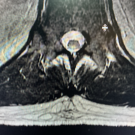

A 49-year-old man presented to the emergency department with a 1-day history of progressive bilateral lower-extremity weakness and an inability to bear weight.